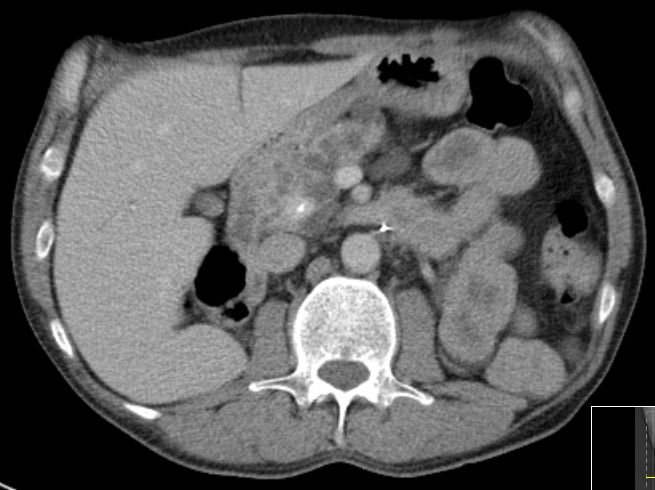

Riesige Zystennieren beiderseits.

Die Zystennieren enthielter beiderseits Nierenzellkarzinome. Die Lungenmetastasierung ist erkennbar.